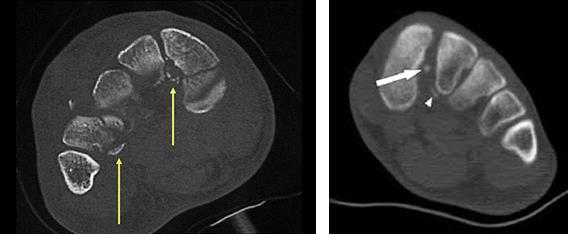

Для диагностики повреждения сустава Шопара делают рентген, КТ и МРТ. На передне-задней рентгенограмме определяют величину пяточно-кубовидного угла. Проводят одну касательную к наружному краю кубовидной кости и вторую касательную к наружному краю пяточной кости. В норме угол между касательными колеблется в пределах от 0 до 5°. Увеличение угла свидетельствует о нарушении стабильности пяточно-кубовидного сочленения. КТ во фронтальной и сагиттальной плоскостях позволяет выявить дефект суставных фасеток, смещение костей при вывихе и фрагментацию костей при переломе. КТ, по сравнению с рентгенографией, является более информативным методом диагностики. МРТ позволяет выявить дефекты отдельных связок.

В сложных с диагностической точки зрения случаях целесообразно использование КТ и МРТ.